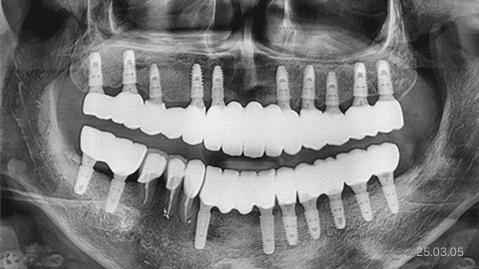

뼈이식 · 전체 임플란트

잇몸뼈 부족 · 타 치과 임플란트 불가판정 · 장기간 틀니 사용

*위 사진은 환자 본인 동의를 얻어 동일 조건에서 촬영 되었습니다. 모든 치료에는 부작용이 발생할 수가 있습니다.